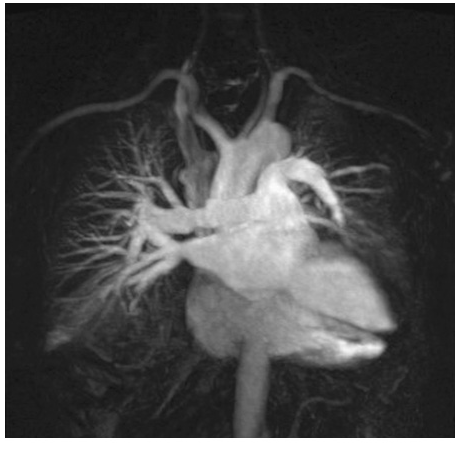

The role of magnetic resonance (MR) imaging in the evaluation of respiratory system disease is less well-defined than that of CT. Magnetic resonance provides poorer spatial resolution and less detail of the pulmonary parenchyma, and for these reasons is currently not considered a substitute for CT in imaging the thorax. However, the use of hyperpolarized gas in conjunction with MR has led to the investigational use of MR for imaging the lungs, particularly in obstructive lung disease. Of note, MR examinations are difficult to obtain among several subgroups of patients. Patients who cannot lie still or who cannot lie on their backs may have MR images that are of poor quality; some tests require patients to hold their breaths for 15 to 25 seconds at a time in order to get good MR images. MR is generally avoided in unstable and/or ventilated patients and those with severe trauma because of the hazards of the MR environment and the difficulties in monitoring patients within the MR room. The presence of metallic foreign bodies, pacemakers, and intracranial aneurysm clips also preclude use of MR.

An advantage of MR is the use of nonionizing electromagnetic radiation. Additionally, MR is well suited to distinguish vascular from nonvascular structures without the need for contrast. Blood vessels appear as hollow tubular structures because flowing blood does not produce a signal on MR imaging. Therefore, MR can be useful in demonstrating pulmonary emboli, defining aortic lesions such as aneurysms or dissection, or other vascular abnormalities (Fig. C-5) if radiation and IV contrast medium cannot be used. Gadolinium can be used as an intravascular contrast agent for MR angiography (MRA); however, synchronization of data acquisition with the peak arterial bolus is one of the major challenges of MRA; the flow of contrast medium from the peripheral injection site to the vessel of interest is affected by a number of factors including heart rate, stroke volume, and the presence of proximal stenotic lesions.